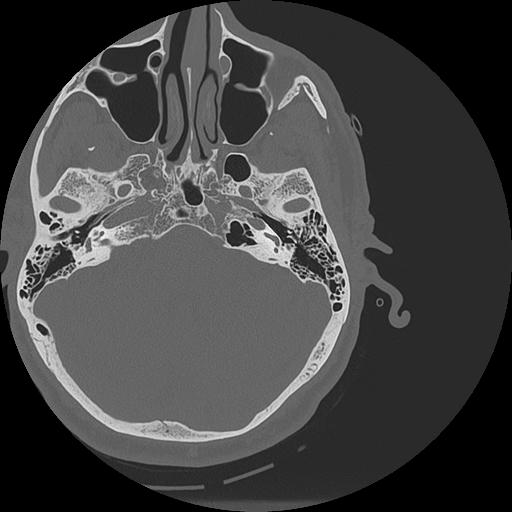

7 HUESO,,Vol,0.5,HUESO,,